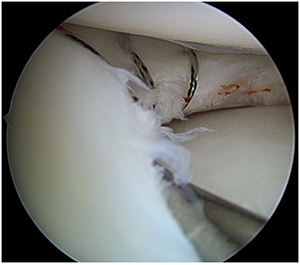

図1:関節鏡:前十字靱帯再建術

図2:関節鏡:半月板縫合術